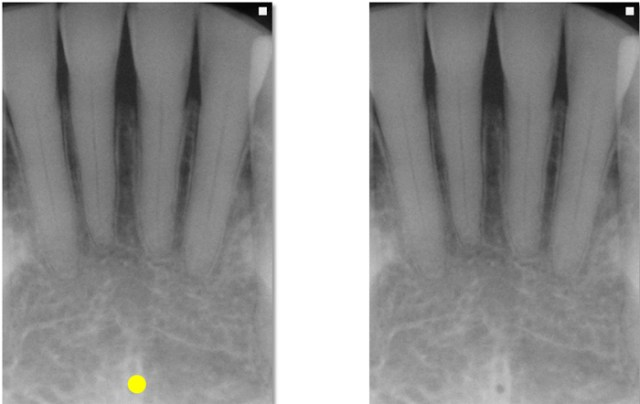

small radiolucent dot located inferior to the apices of mandibular incisors, may be seen

what is this, its description and its appearance on images

genial tubercles

tiny bumps of bone located on lingual aspect of mandible

ringshaped radiopacity surrounding lingual foramen, may be viewed